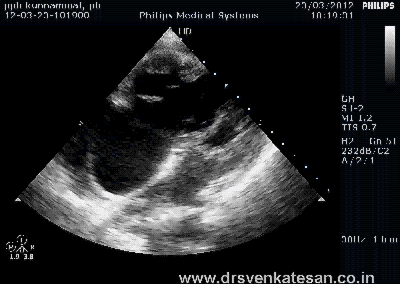

We know RV has a unique shape triangular ( partially pyramidal ) . It can be inferred the RV cavity is formed by fusion of many eccentric spacial planes. We have always believed RV handles the blood it receives from right atrium in a unique way .Now we are beginning to understand it .It is now documented the RV segregates the blood it receives into 4 components.

It is curious to know RV inflow is connected to the outflow by an invisible physiologic Bridge . About 44% of blood traverse the RV in this fashion.

Note : RV blood flow preferentially enters the RVOT with out transiting RV body and apex.Image courtesy http://ajpheart.physiology.org/

Which is the most important part in RV ? (Among Inflow, Body, Apex, Out flow)

After reading this article it seems to me , the mechanical function of RVOT could be most vital. If it fails to handle the first increment which comes directly from RV inflow, stasis is likely in RV body and apex , elevating RVEDP and later promoting stasis leading to clinical events.